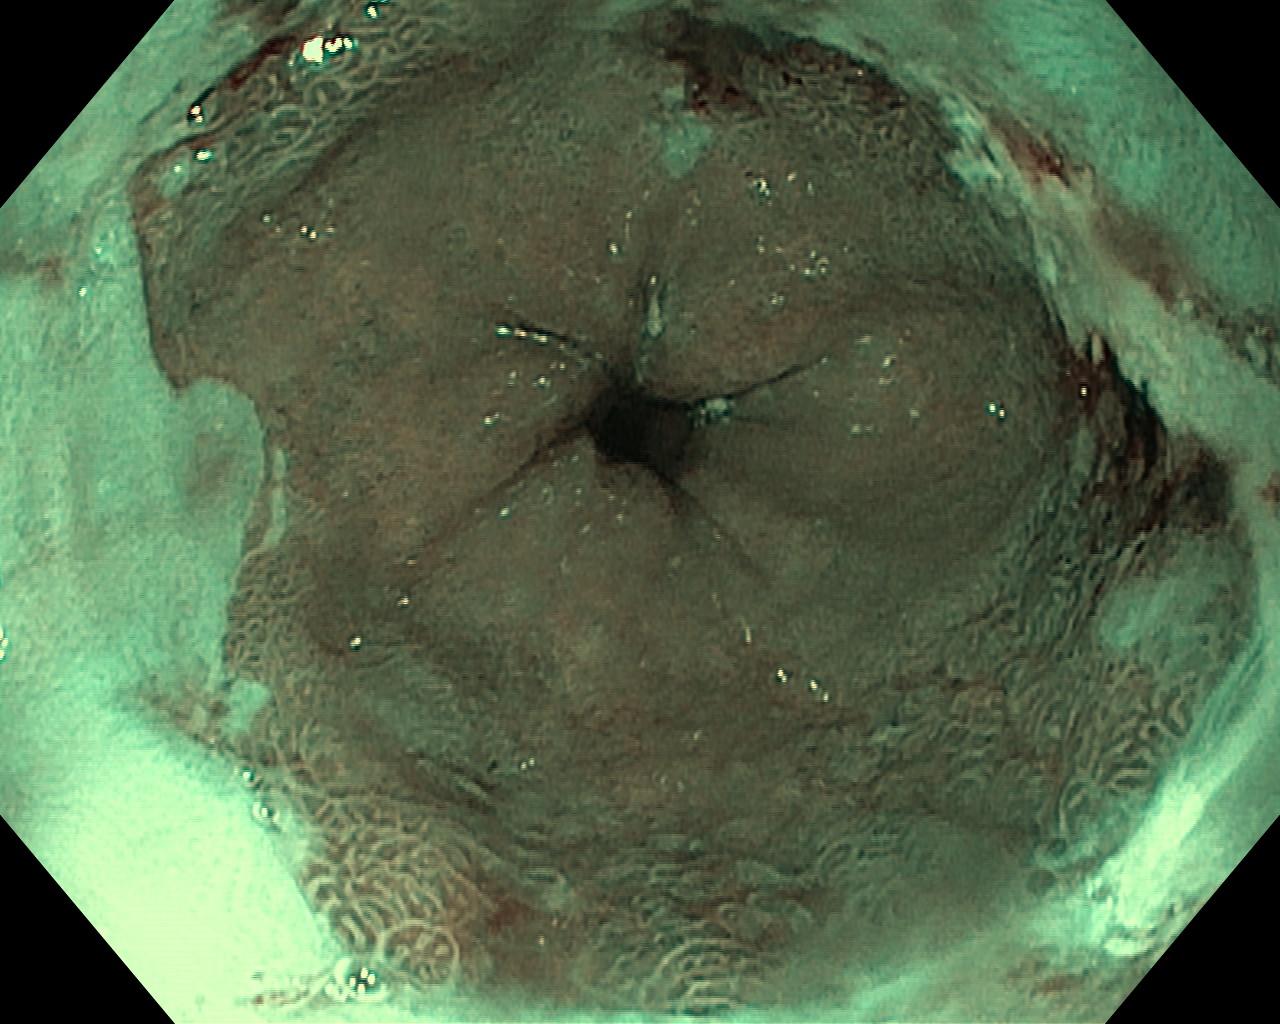

Przełyk Barretta